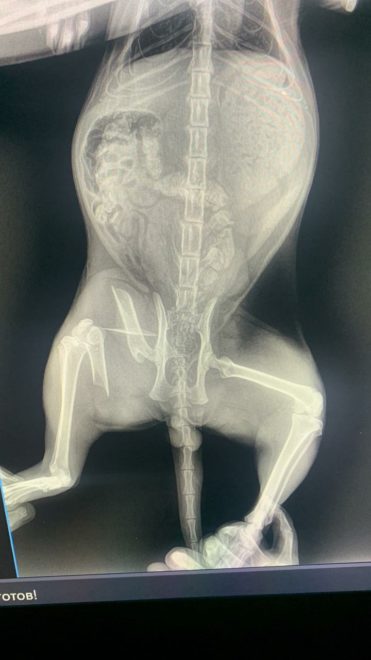

Кота отвезли в клинику, где после осмотра выяснилось, что у животного серьезный перелом. Волонтеры решили доставить кота в город Торжок, где врачи уже «собирали» другого переломанного подопечного. В Торжке врач три часа оперировал кота, собирая лапу, но в итоге смог это сделать. Теперь избитому коту предстоит два месяца носить крепление, если дела пойдут хорошо.

Также сообщается, что по словам ветеринара, ко получил направленный удар каким-то предметом, что и вызвало перелом.